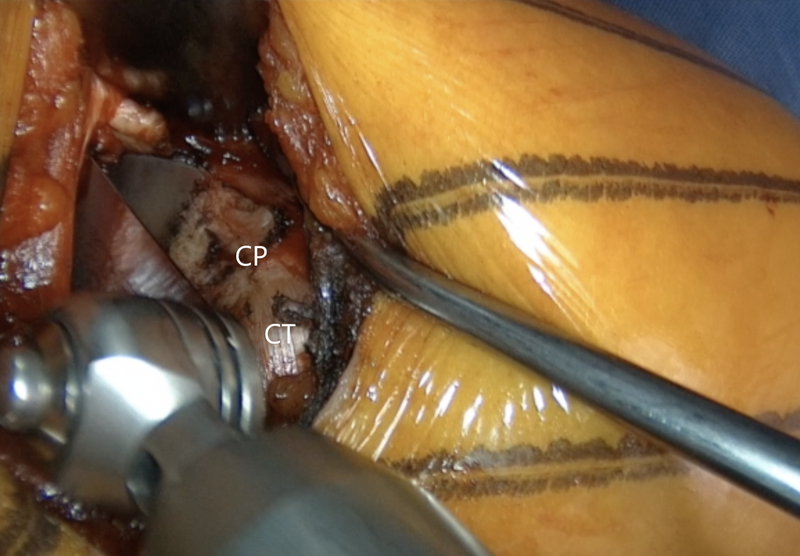

Left shoulder of a patient placed in a semi beach-chair position. A 90° angled saw blade is used for coracoid osteotomy, which is performed at the base of the coracoid process (CP) as far back as possible, however still in front of the coracoclavicular ligaments. CT – conjoined tendon.